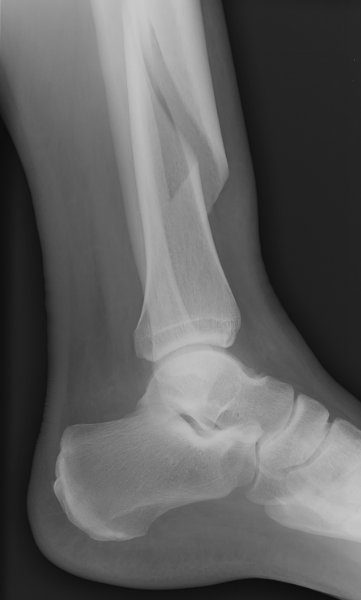

Return to Tibial Shaft Fracture